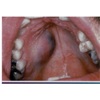

Mucoepidermoid carcinoma. 小孩大人最常見的惡性腫瘤(PA多型腺瘤最常見的良性腫瘤 好像也是小孩大人)腫瘤細胞常出現CRTC1-MAML2基因轉位 腫瘤中常可見黏液細胞、表皮樣細胞及中間型細胞